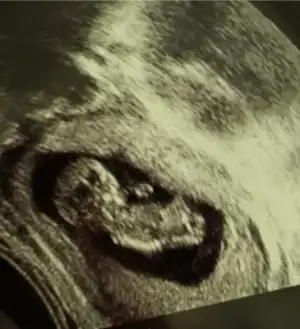

dün 2 li tarama testine girdim bebeğim uyuyordu doktor cinsiyet tahmini yapmadı renkli ultrasonografi görüntülerim var, bu resimlere göre cinsiyet tahmini yapabilirmsiiniz , bu ikinci gebeliğim 8,5 yaşında bir kızım var

mesajım görünmüyor mu acaba cevap alamadım, 12+5 de 2 li tarama yaptırdım, cinsiyet tahmini yapmadılar, bu görüntüler üzerinden tahmin yapabilirmisiniz

Belkide kızdır çünkü çıkıntı gördüğüm nub ise erkek sanki dedim başka USG varmi